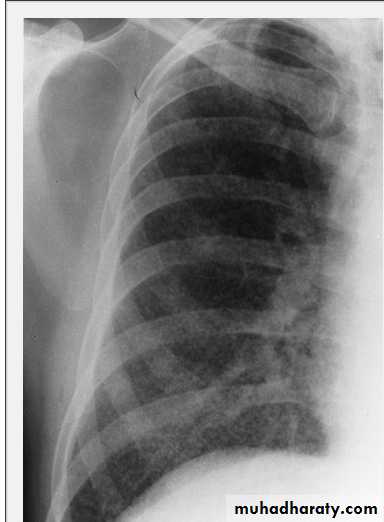

• LOBAR PNEUMONIA

Right lower lobe consolidation - PA. Dense opacification in the right lower zone with effacement of the outline of the right hemidiaphragm.